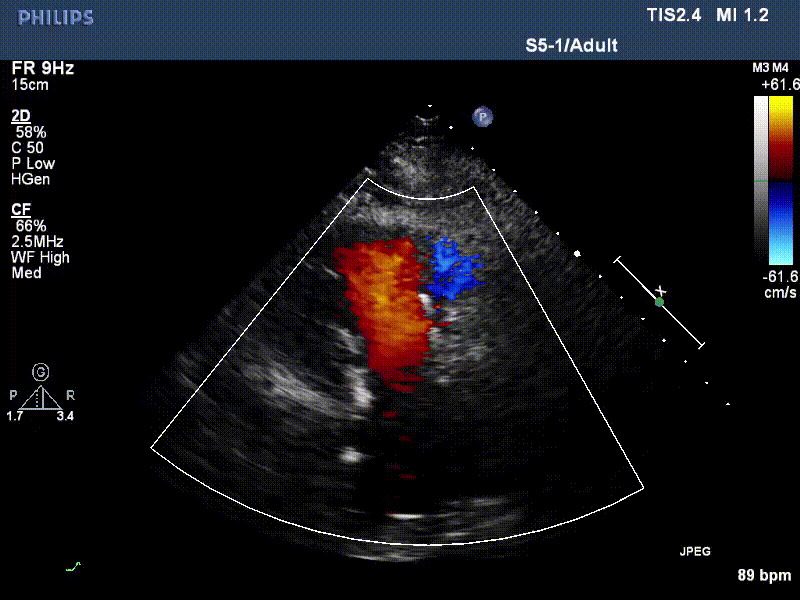

流并分別伴有房顫和房撲,高外科手術(shù)風(fēng)險。術(shù)前超聲提示,兩例患者下腔靜脈寬度分別為13mm和29mm,右房內(nèi)徑(上下徑和左右徑)分別為52×41mm和53×43mm,彩色多普勒顯示極重度三尖瓣反流,VCW分別為14×15mm和10mm。

1年前,兩例患者因難治性雙下肢水腫輾轉(zhuǎn)多家醫(yī)院尋求救治,考慮到兩例患者高齡、基礎(chǔ)疾病多、STS評分高,不適合傳統(tǒng)外科開胸手術(shù),葛均波院士及其團(tuán)隊周達(dá)新教授、潘文志教授、張源博士、陳莎莎博士、陳丹丹博士聯(lián)合心外科王春生、魏來主任,麻醉科繆長虹、郭克芳主任以及心超室的潘翠珍教授、李偉教授共同討論決定,采用我國創(chuàng)新器械LuX-Valve Plus經(jīng)血管三尖瓣置換系統(tǒng)為患者進(jìn)行手術(shù)。相較于第一代產(chǎn)品LuX-Valve,LuX-Valve Plus經(jīng)血管三尖瓣置換系統(tǒng)對輸送系統(tǒng)進(jìn)行了全面升級,實現(xiàn)了經(jīng)頸靜脈入路的方式,進(jìn)一步減小了手術(shù)風(fēng)險和對患者的創(chuàng)傷。目前隨訪1年心超結(jié)果顯示,三尖瓣極重度反流消失,人工三尖瓣瓣膜穩(wěn)定牢固,瓣葉活動度良好,右心室及下腔靜脈明顯縮小,心輸出量增加。兩位老人手術(shù)后沒有出現(xiàn)過胸悶氣促的癥狀,下肢水腫緩解,活動耐力提升,生活質(zhì)量也大為提高。

圖2 患者植入LuX-Valve Plus后,1年隨訪心超提示無三尖瓣反流